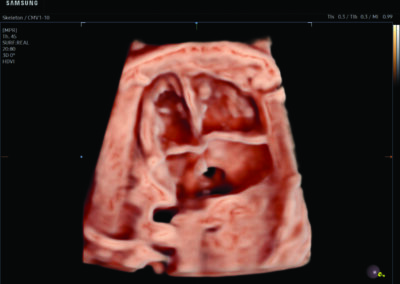

Procedural Services

Comprehensive, advanced and expert MFM care for high-risk pregnancies

- Fetal anomalies